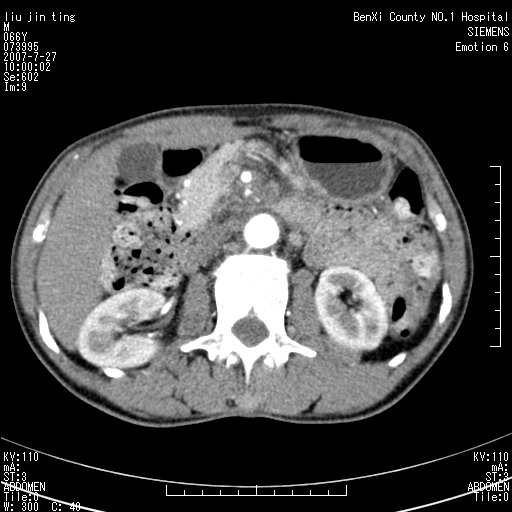

腹痛,背痛,无恶心呕吐,不黄,彩超示胰腺钩癌,ct扫描病灶平扫30-40hu,增强后动脉期40--60hu,静脉期50-68hu,真的是钩突上的么?您要试一试么?

动脉期

静脉期

沿着肠系膜上动脉呈匍匐性生长的软组织肿块,形态不规则,包绕肠系膜上动脉,呈明显强化,考虑来源于肠系膜的恶性肿瘤

沿着肠系膜上动脉呈匍匐性生长的软组织肿块,形态不规则,包绕肠系膜上动脉,呈轻-中度强化,考虑来源于肠系膜的恶性肿瘤。